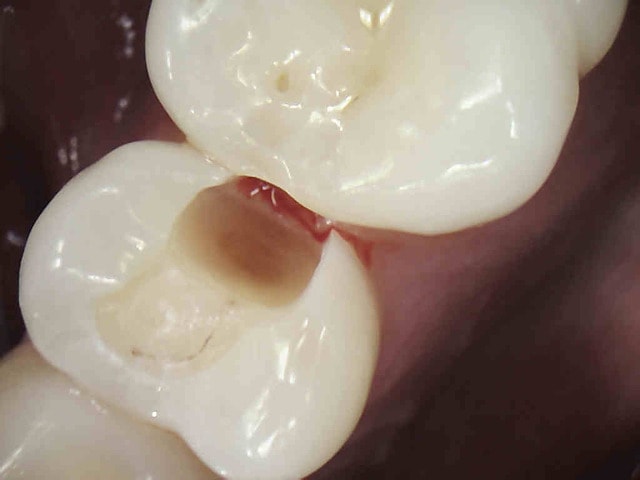

J'y travaille pour trouver un moyen simple et efficace pour poser la digue dans toutes les situations comme celle ci dessous. Tiens c'est tout frais, endo sc33 en 1 temps, 1H 15 et encore je n'ai pas d'assistante au fauteuil.

Pulpite indication endo. perte de substance: Indication onlay , mais pas dans le panier de soins donc sc 33, couronne coulée : patiente CMU.

Dis donc chicot t'es peut être le roi de l'endo mais au niveau économie tissulaire , ouverture de chambre , tu utilises un black et decker comme contre angle ?... t'y vas pas de main morte ... t'aurais peut être pu éviter le tenon alors , et qui sait la couronne .... et puis un genre screw post titane ? avec un matériau plastique perso je trouve pas ça terrible ... mais je ne suis qu'une petite dentiste qui utilise encore l'amalgame ... houuuu la méchante .....bon et puis la (ou le ) mitrailler comme ça pendant le soin juste pour nous montrer , faut pas tu sais , tu perds un temps fou ... après le temps de poster tout ça ..... t'imagines le temps perdu pour la rentabilité du cabinet ....